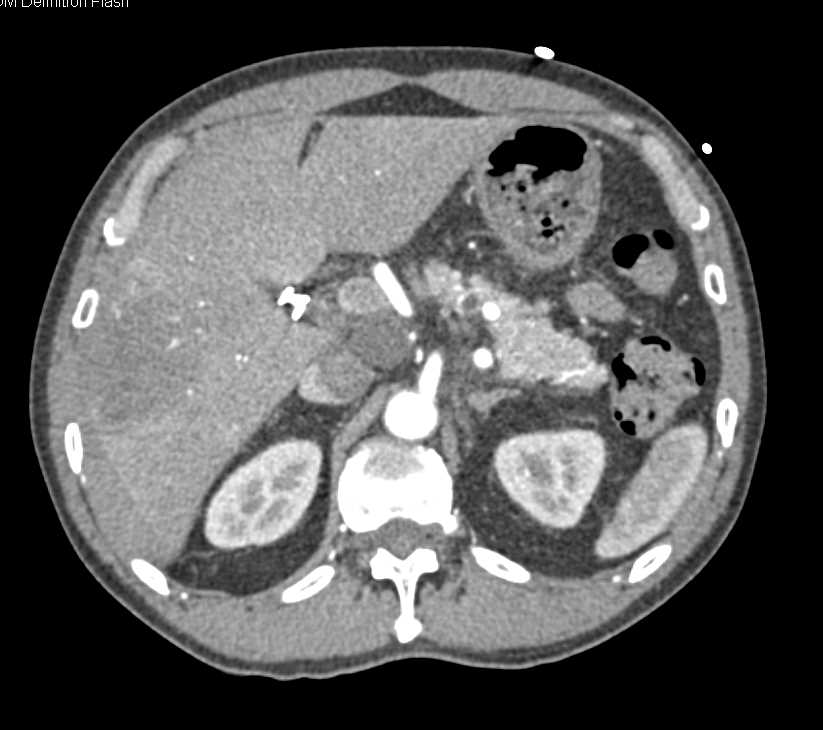

Carcinoma Gastroesophageal (GE) Junction with Metastases